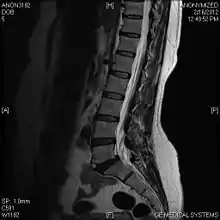

Limbus vertebra

A limbus vertebra is a bone tubercle formed by bone trauma on a vertebral body, bearing a radiographic similarity to a vertebral fracture. The anterior-superior corner of a single vertebra is the common site for this defect although it can also be seen at the inferior corner as well as the posterior or anterior margin. Anatomically, it is assumed to be an intra-vertebral body herniation of the disc material occurring during adolescent growth spurt when the ring apophysis has not yet fused. It was first described by Schmorl in 1927 and later in detail by Leif Sward and Adad baranto.

Viewed in a lateral radiograph, it appears as a triangular shaped bone fragment, not unlike an anterior lip fracture, but with softer edges.

Limbus vertebra is not always symptomatic, but severe cases may lead to more serious pathological conditions and chronic pain. In rare instances, a posterior limbus vertebra has been described causing radiculopathy due to nerve root compression.